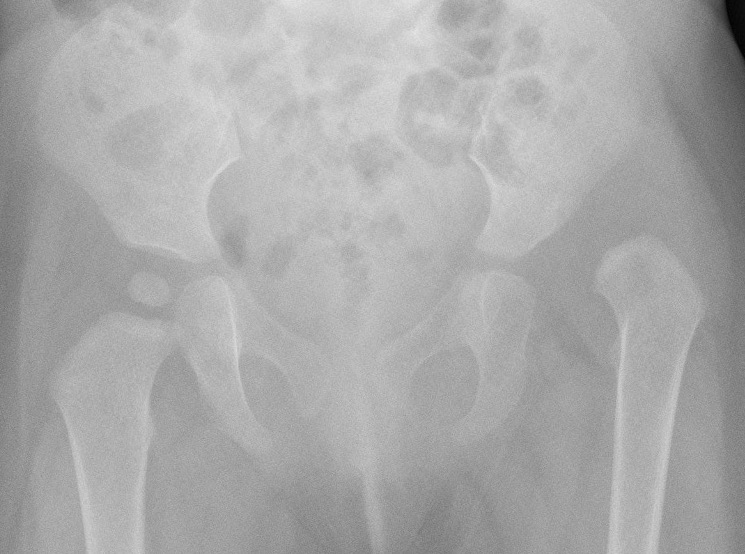

Xray

Dislocated hips in the setting of DDH with ncreased acetabular index